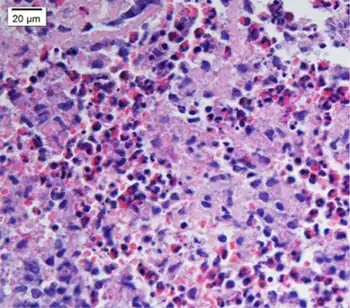

| Biopsy shows remarkable eosinophilic cell infiltration at interstitium of myocardium and necrosis of myocardium | |